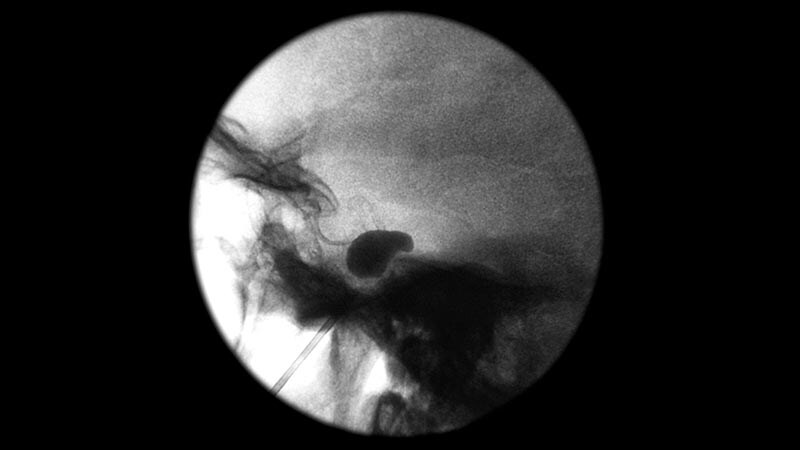

Migraine